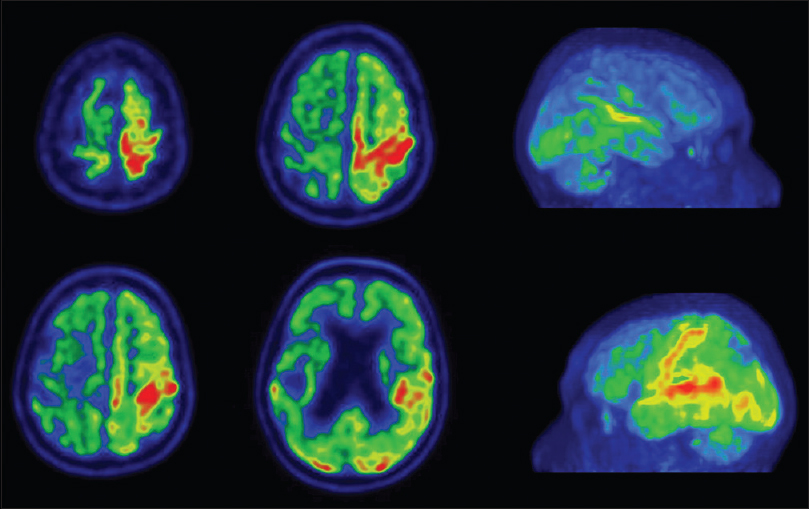

Corticobasal Degeneration Mri Findings

Foundation Text Neuroimaging: Visualizing Brain Structure and Function

Frontiers REM-Sleep Behavior Disorder in Patients With Essential Tremor: What Is